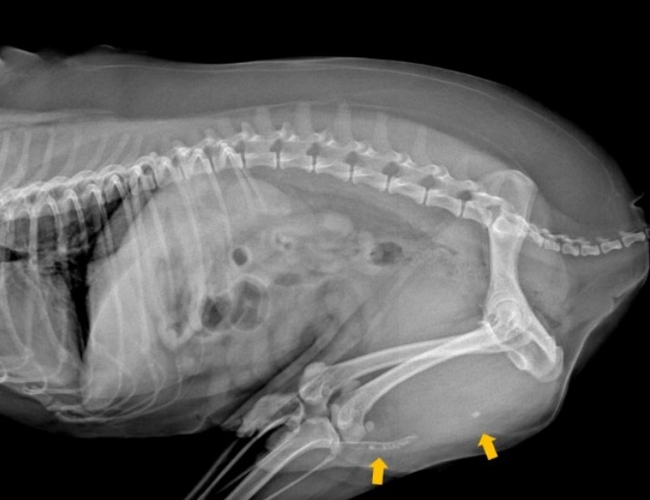

푸딩이의 상태를 정확히 알고자 방사선과 초음파 검사를 진행했습니다.

VIP동물의료센터 동대문점 영상의학과 의료진이 정밀하게 검사하고 진단했습니다.

방사선과 초음파 검사 결과 상 푸딩이의 요도 내 결석이 또렷하게 확인되었습니다.